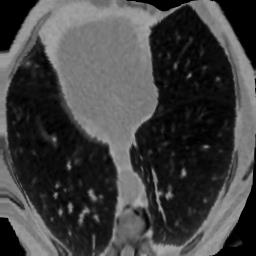

In clinical practice, well-aligned multi-modal images, such as Magnetic Resonance (MR) and Computed Tomography (CT), together can provide complementary information for image-guided therapies. Multi-modal image registration is essential for the accurate alignment of these multi-modal images. However, it remains a very challenging task due to complicated and unknown spatial correspondence between different modalities. In this paper, we propose a novel translation-based unsupervised deformable image registration approach to convert the multi-modal registration problem to a mono-modal one. Specifically, our approach incorporates a discriminator-free translation network to facilitate the training of the registration network and a patchwise contrastive loss to encourage the translation network to preserve object shapes. Furthermore, we propose to replace an adversarial loss, that is widely used in previous multi-modal image registration methods, with a pixel loss in order to integrate the output of translation into the target modality. This leads to an unsupervised method requiring no ground-truth deformation or pairs of aligned images for training. We evaluate four variants of our approach on the public Learn2Reg 2021 datasets \cite{hering2021learn2reg}. The experimental results demonstrate that the proposed architecture achieves state-of-the-art performance. Our code is available at https://github.com/heyblackC/DFMIR.